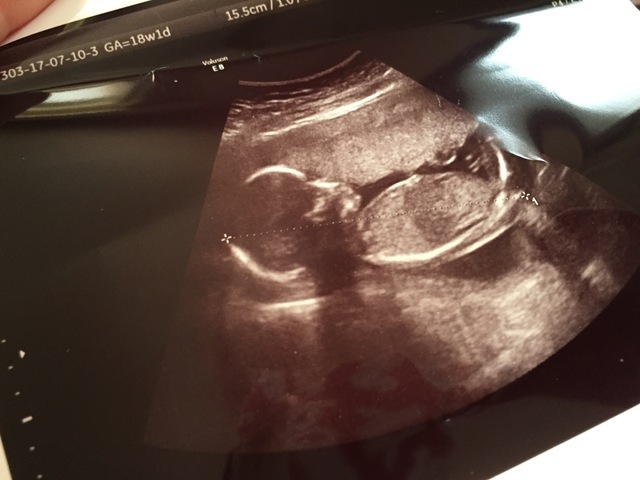

18週4日(18w4d・女の子)|桐 さん(28歳)

エコー写真撮影時のエピソード:

最初のエコー写真は、点しか写ってなくて少しずつ人の形になっていく事にとても感動した! 応募したエコー写真は、全体が写った最後の写真!

次から身体の一部ずつしか写らなくなってお腹の中に命がもう1つあるんだなと成長してるんだなと不思議な気持ちです。